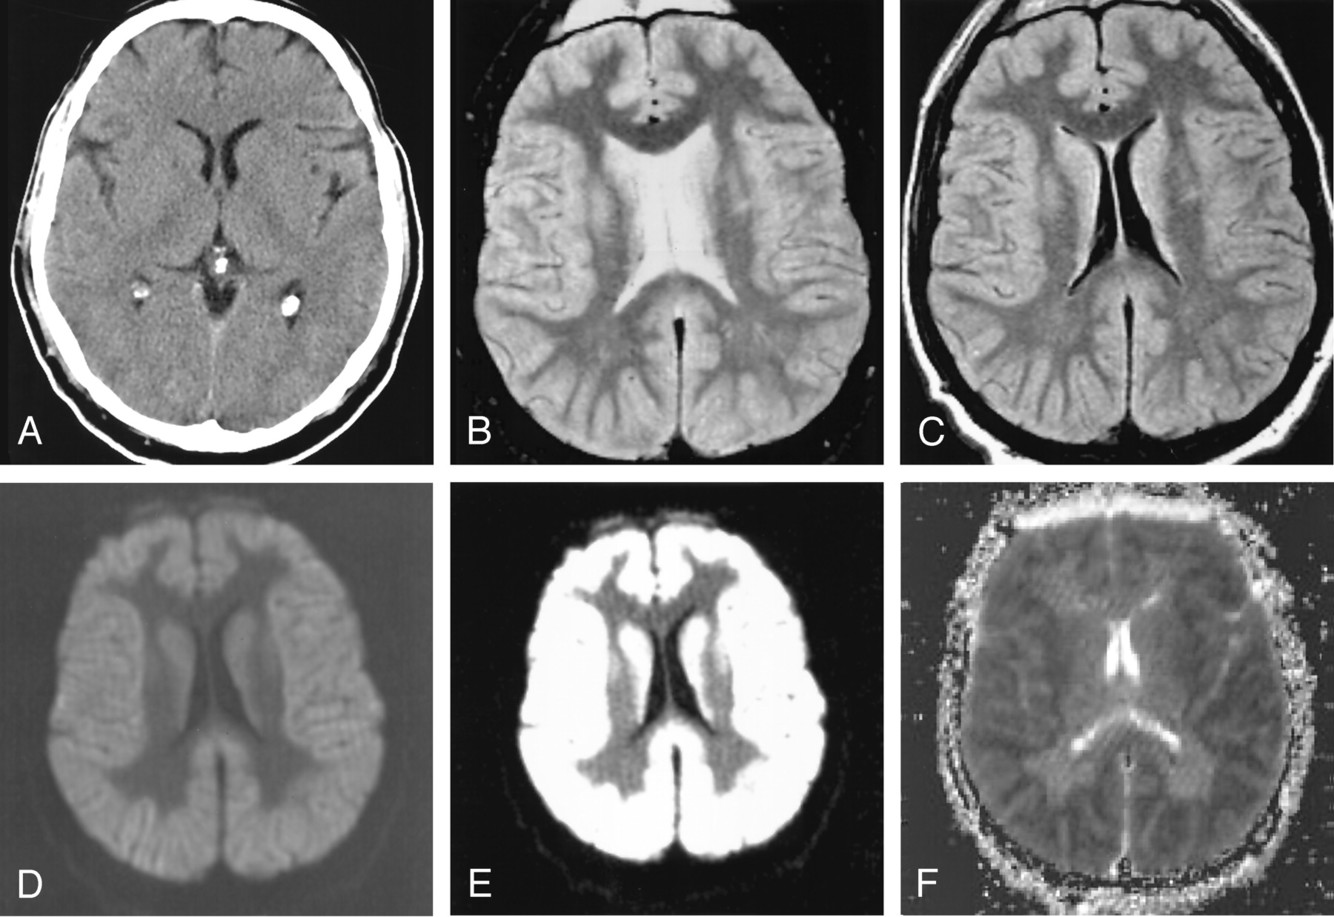

A 20 year old man tries to commit suicide by hanging himself. He is cut down after several minutes and is pulseless. He is resuscitated and regains a heartbeat and respiratory drive and cough to suctioning. Three days later, his exam has not changed.

Where is the lesion?

cortical lamniar necrosis

Neurons survive 6-10 mins w/out oxygen and glial cells last up to mins

glial cells liver 30 mins

astrocytyes live longer